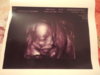

jestem w szoku, jak Bąbelek urósł od ostatniego usg, poprzednio miał 5 mm wielkości i przypominał małą fasolkę a teraz, szok, 4,6 cm, rączki, nóżki, serducho bije jak dzwon! z aktualnego usg wychodzi, że to 11 tydzień 2 dzień. Czy to możliwe, że Bąbel aż tyle nadrobił od ostatniego usg???

Drogie cioteczki, Bąbelek chyba specjalnie dla Was tak ładnie zapozował ;-)

Zobacz załącznik 599948